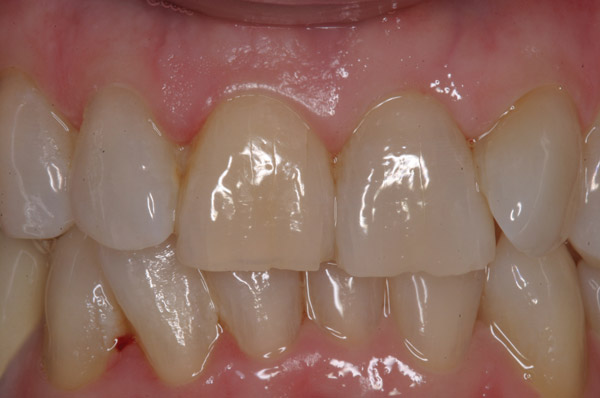

Figure 19  The post-implantation and post-restoration view shows esthetically pleasing, symmetric crowns and mucosal contours, with the Nos. 7 and 10 implant prostheses blending in imperceptibly with the natural dentition. Restoration courtesy of Dr. Jeffrey Warren.

Figure 19